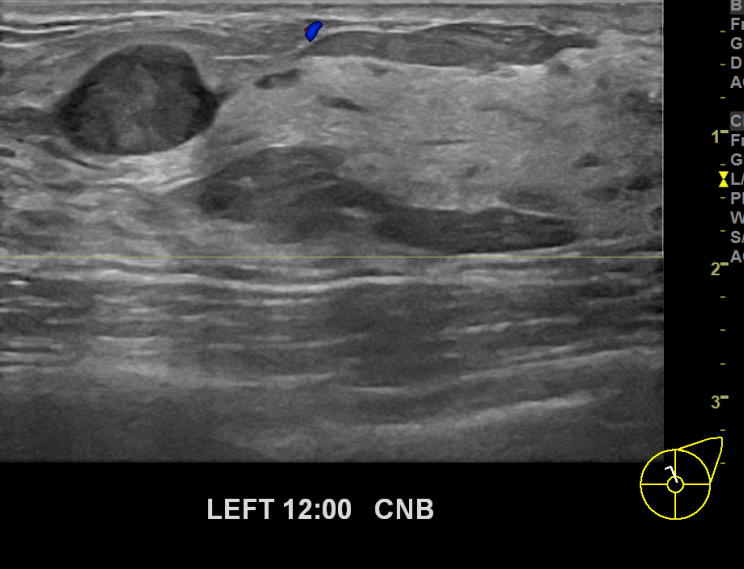

아산유외과개원후 682번째 유방암진단

상기환자 외부건진상이상소견으로 내원하신30대여성분으로 좌측유방

의심스러운 혹 조직검사시행후 유방암 진단되었습니다